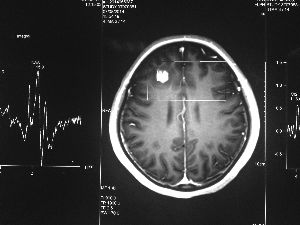

方框亮點為CT片顯示的異物

今年6月份,張敏在宿舍休息時,又發起了癲癇,也是口吐白沫,渾身抽搐。送到蘇州一家大醫院,頭顱核磁共振檢查出,張敏大腦右額葉處有一處病灶,也就是大腦額頭處有個東西。

腦袋里的東西,到底是腫瘤還是其他什么東西,這個謎像個石頭一樣,壓得張敏一家人喘不過氣。7月份,張敏一家又來到南京腦科醫院求醫,第三次檢查后,醫生覺得很像是寄生蟲。不過,影像的檢查,只能作為醫生推測的依據,具體是什么,只有手術拿出來后才能知道。